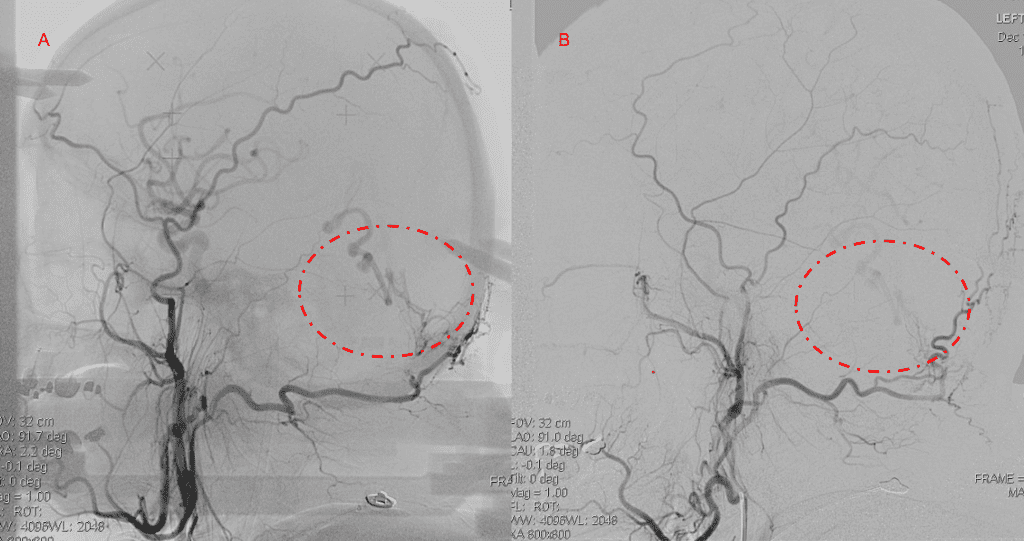

Figure 3. Right ECA AP and Lateral angiograms Pre (A and B) and Post NBCA embolization (C and D) Demonstrate near complete obliteration of right Occipital and Middle Meningeal Artery Fistulas

Embolization was successful at immediately reducing the pressure into the Aneurysmal Varix with greater than 90% reduction in A-V shunts. After an intensive period of critical care monitoring and care for her initial brain hemorrhage, she made a near complete recovery with mild intermittent left sided paresthesias and generalized deconditioning. After receiving inpatient and outpatient Acute Rehabilitation, Physical, and Occupational therapy, she completely recovered all of her Activities of Daily Living (ADLs) at 3 months and achieved an modified Rankin Scale (mRS) of 0. On follow-up angiography, small residual low flow A-V shunts were identified and targeted for Gamma Knife Radiosurgery (Figure 5 and 6).